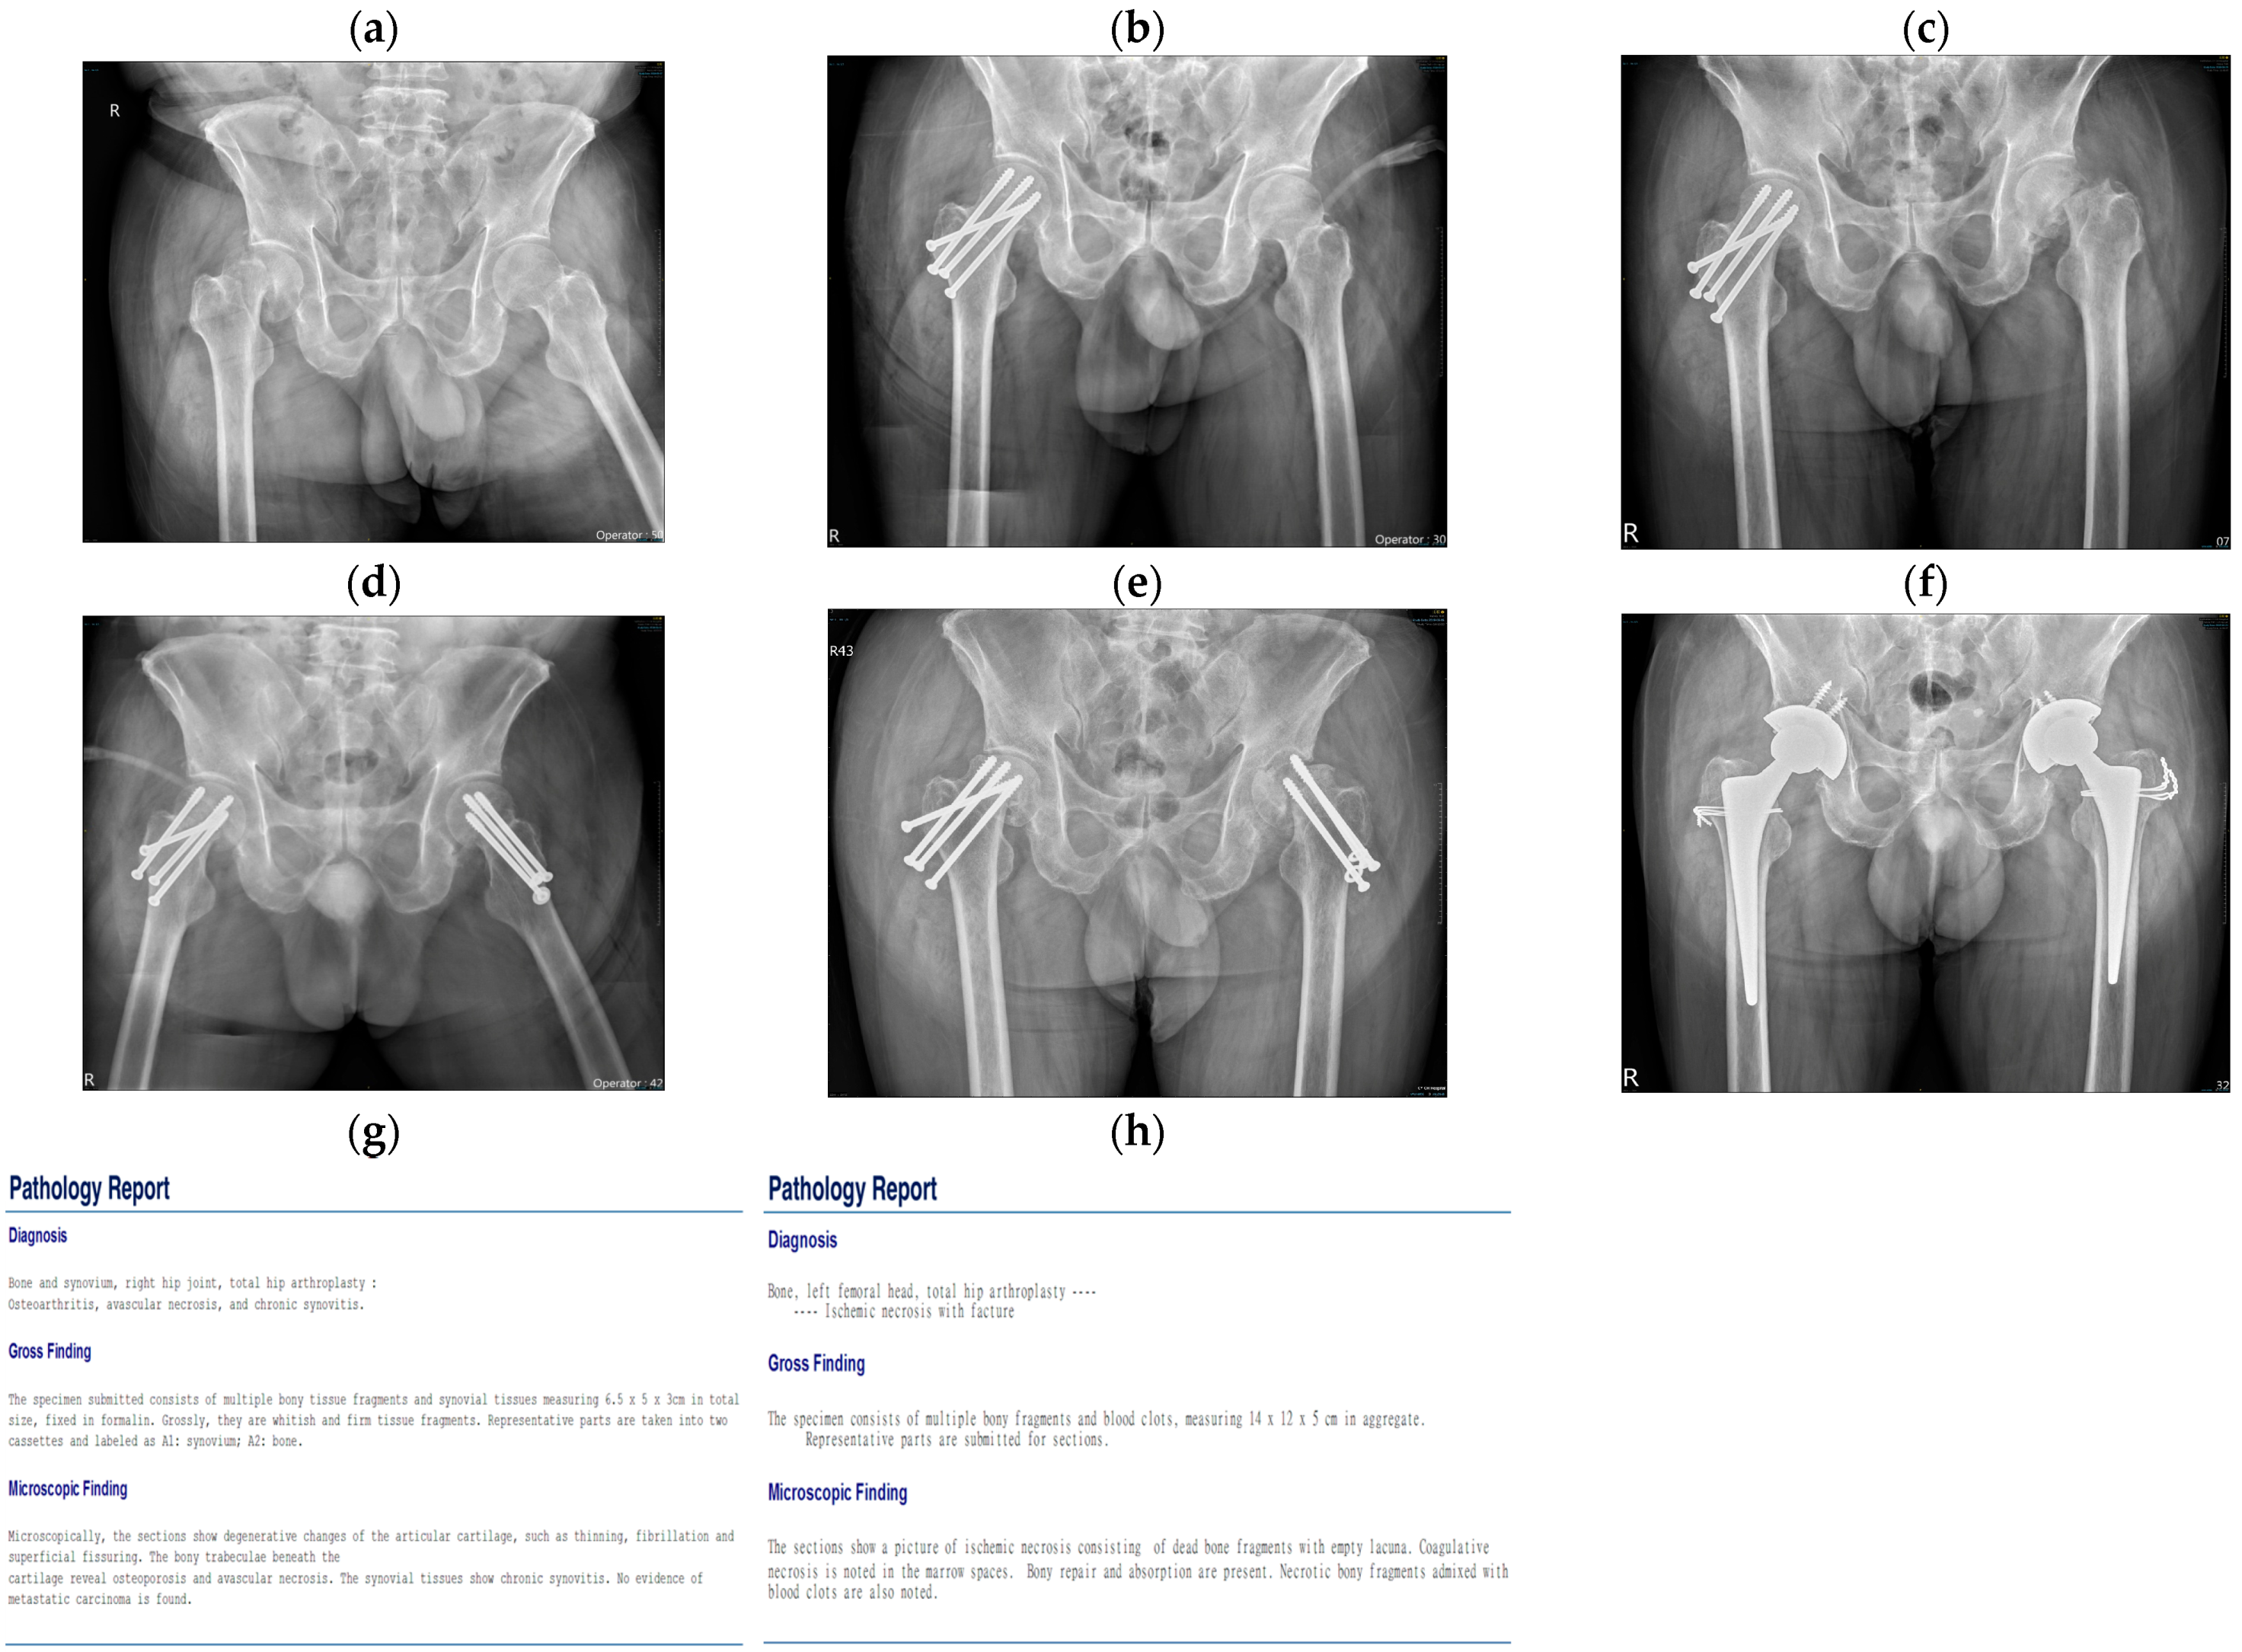

| No. 1 | 55 | Male | Hypertension | Alcoholic | Subcapital | No | X-ray | 1. Cannulated screws 2. THA |